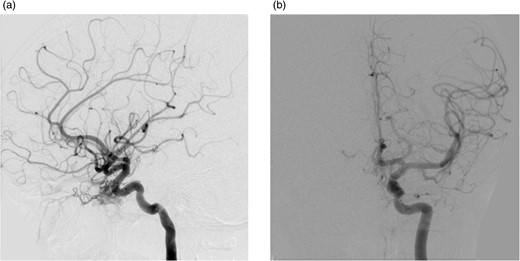

A 12-year-old girl presented with a 7-month history of frontal headaches and intermittent left-sided proptosis. On examination, she had dilated and engorged scleral veins on the left eye (evident on inspection), mild dysdiadochokinesia and past pointing on the left side. A brain computed tomography (CT) with contrast showed an enlarged left superior ophthalmic vein and a prominent left cavernous sinus. An interventional radiography (IR) cerebral angiogram under general anaesthesia was performed, which revealed evidence of an indirect CCF fed by ophthalmic branches of the left internal carotid artery and filling from multiple ethmodial branches of the distal internal maxillary artery. From the fistula, the ophthalmic vein was markedly hypertrophied and drained the cavernous sinus anteriorly. The fistula was also feeding from the right side through ethmodial branches into the right cavernous sinus and across to the left cavernous sinus (Fig. 2).